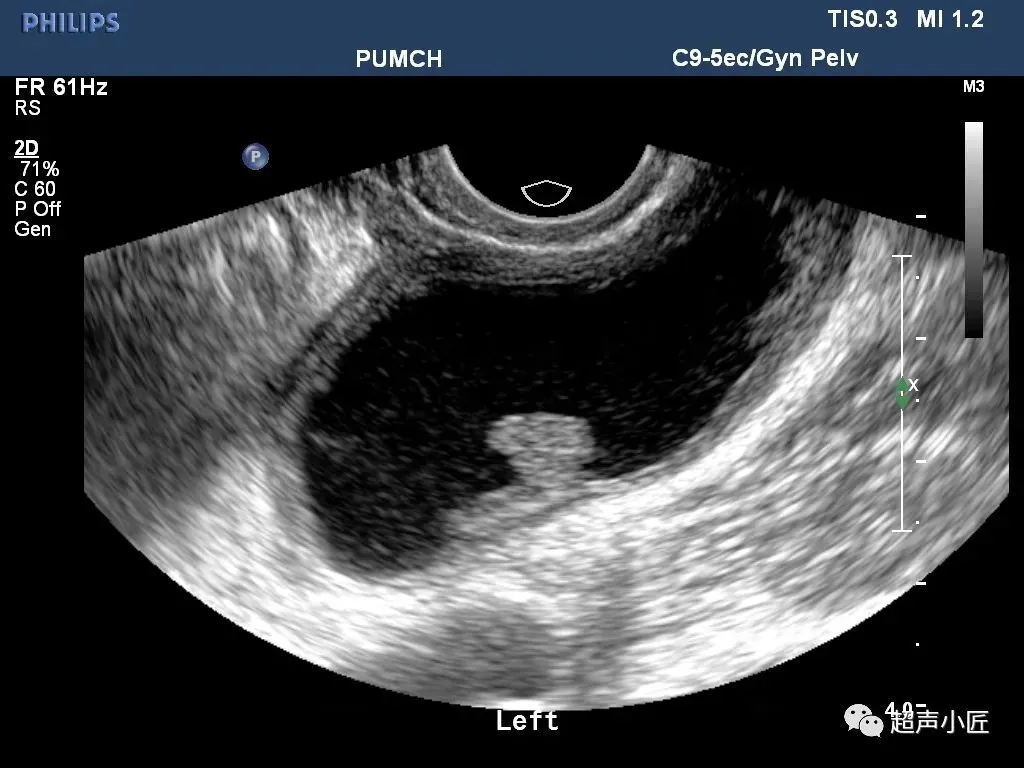

黏膜下肌瘤

经阴道超声扫查表现为子宫内膜变形或缺损,内膜下肌层可见低回声结节突向宫腔,带蒂的粘膜下肌瘤可以突入宫颈管内,形成宫颈管内实性占位声像,仔细扫查可见其与子宫壁有蒂相连,有时呈多发性粘膜下肌瘤。